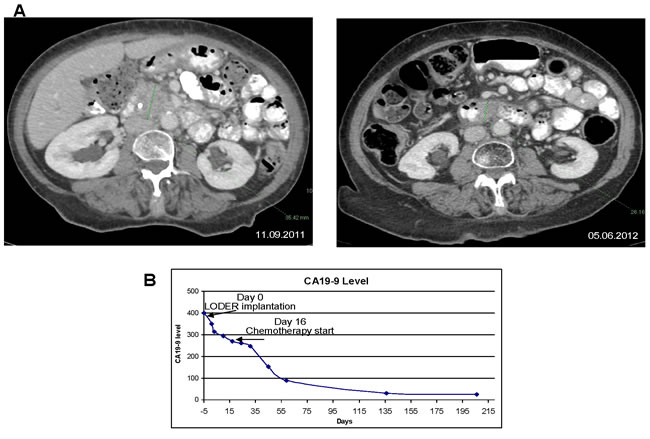

In particular, we present a case of one of the patients from the low dose group. The patient initiated Gemcitabine chemotherapy 16 days after the siG12D-LODERTM implantation. The treatment was well tolerated, with no significant side-effects. The serum-based tumor-marker CA19-9 decreased by 22.4% following the siG12D-LODERTM implantation before the administration of the first line chemotherapy treatment, and eventually reached normal values (Figure 4B). This patient then received local radiation treatment. A CT scan performed nine months post insertion of siG12D showed a significant decrease in tumor size (Figure 4A). This patient had 17.03 months TTM and died 18.21 months after enrollment to the study.

Figure 4: Anti-tumor effect of combination treatment with siG12D-LODERTM in locally advanced non-operable PAC in a patient: A. left panel: a CT scan was performed prior to the implantation of siG12D-LODERTM using EUS; tumor measures 35.42mm in longest diameter; right panel: nine months later a significant tumor mass reduction is shown on a follow-up CT scan, tumor measures 26.16mm in the longest diameter. B. The level of CA19-9 in blood, showing 23% decrease immediately after LODERTM insertion, prior SOC treatment.